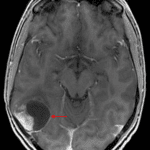

CT

- Mixed attenuation mass with internal calcification centered in the posterior right temporal lobe

- Associated mass effect on the right lateral ventricle without midline shift or hydrocephalus

- Scalloping of the adjacent inner table of the calvarium

MRI

- Mixed cystic/solid mass centered in the posterior right temporal lobe measuring 4.5 x 4 x 3.7 cm

- The solid component avidly enhances and the cystic components demonstrate peripheral enhancement

- The more superior of the two dominant cystic components demonstrates relative T1 signal hyperintensity internally

- Areas of susceptibility artifact corresponding with areas of calcification on the CT

- The mass broadly contacts the overlying dura and the ependymal margin of the atrium of the right lateral ventricle, appearing to contact the choroid plexus

- Mild surrounding vasogenic edema

Pleomorphic xanthoastrocytoma (PXA)